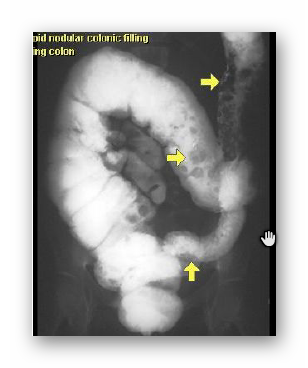

COLITIS ULCEROSA

WLEW DOODBYTNICZY